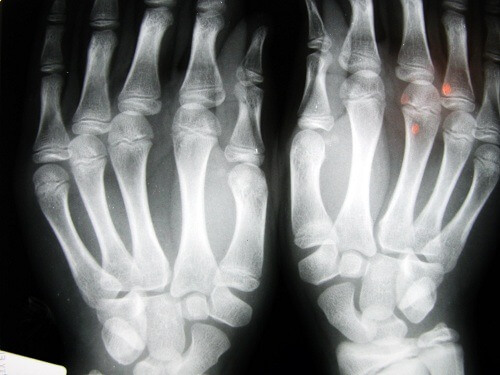

Извършвани са опити за анализиране на хора, които често пукат кокалчетата си. Целта е била да се изясни дали това е довело до щети в ставите, като артрит или остеоартрит.

Това, което е било открито по време на изследването е, че пръстите са показали признаци на увреда. Тя е била най-вече в меките тъкани, наблюдавало се е и намалена способност за хващане на даден обект. Това изглежда е резултат на бързото и повтарящо разтягане и свиване на свързаните сухожилия.

Това може да доведе не само до разрушаване на ставите, но също така и до по-голяма възможност от възникване на напукани или счупени кости. Други от последиците са скованост, деформация на пострадалия район, както и остра болка, която отминава с повече почивка.

Хората, които страдат най-много от този проблем са лица над 40-годишна възраст. Областите, в които се появяват резултатите от пукането на ставите са ръцете (пръстите на ръцете и китките) и областта на шията.

Друго проучване изследва 30 възрастни хора в старчески дом в Лос Анджелис. Тези, които са пукали кокалчетата си цял живот не са получили остеоартрит. При трето проучване, този път с възрастни на 45 години в Детройт е установено, че основния проблем, който възниква е загуба на сила в захващането им и също така над 80% от изследваните страдат от подуване на ръцете.